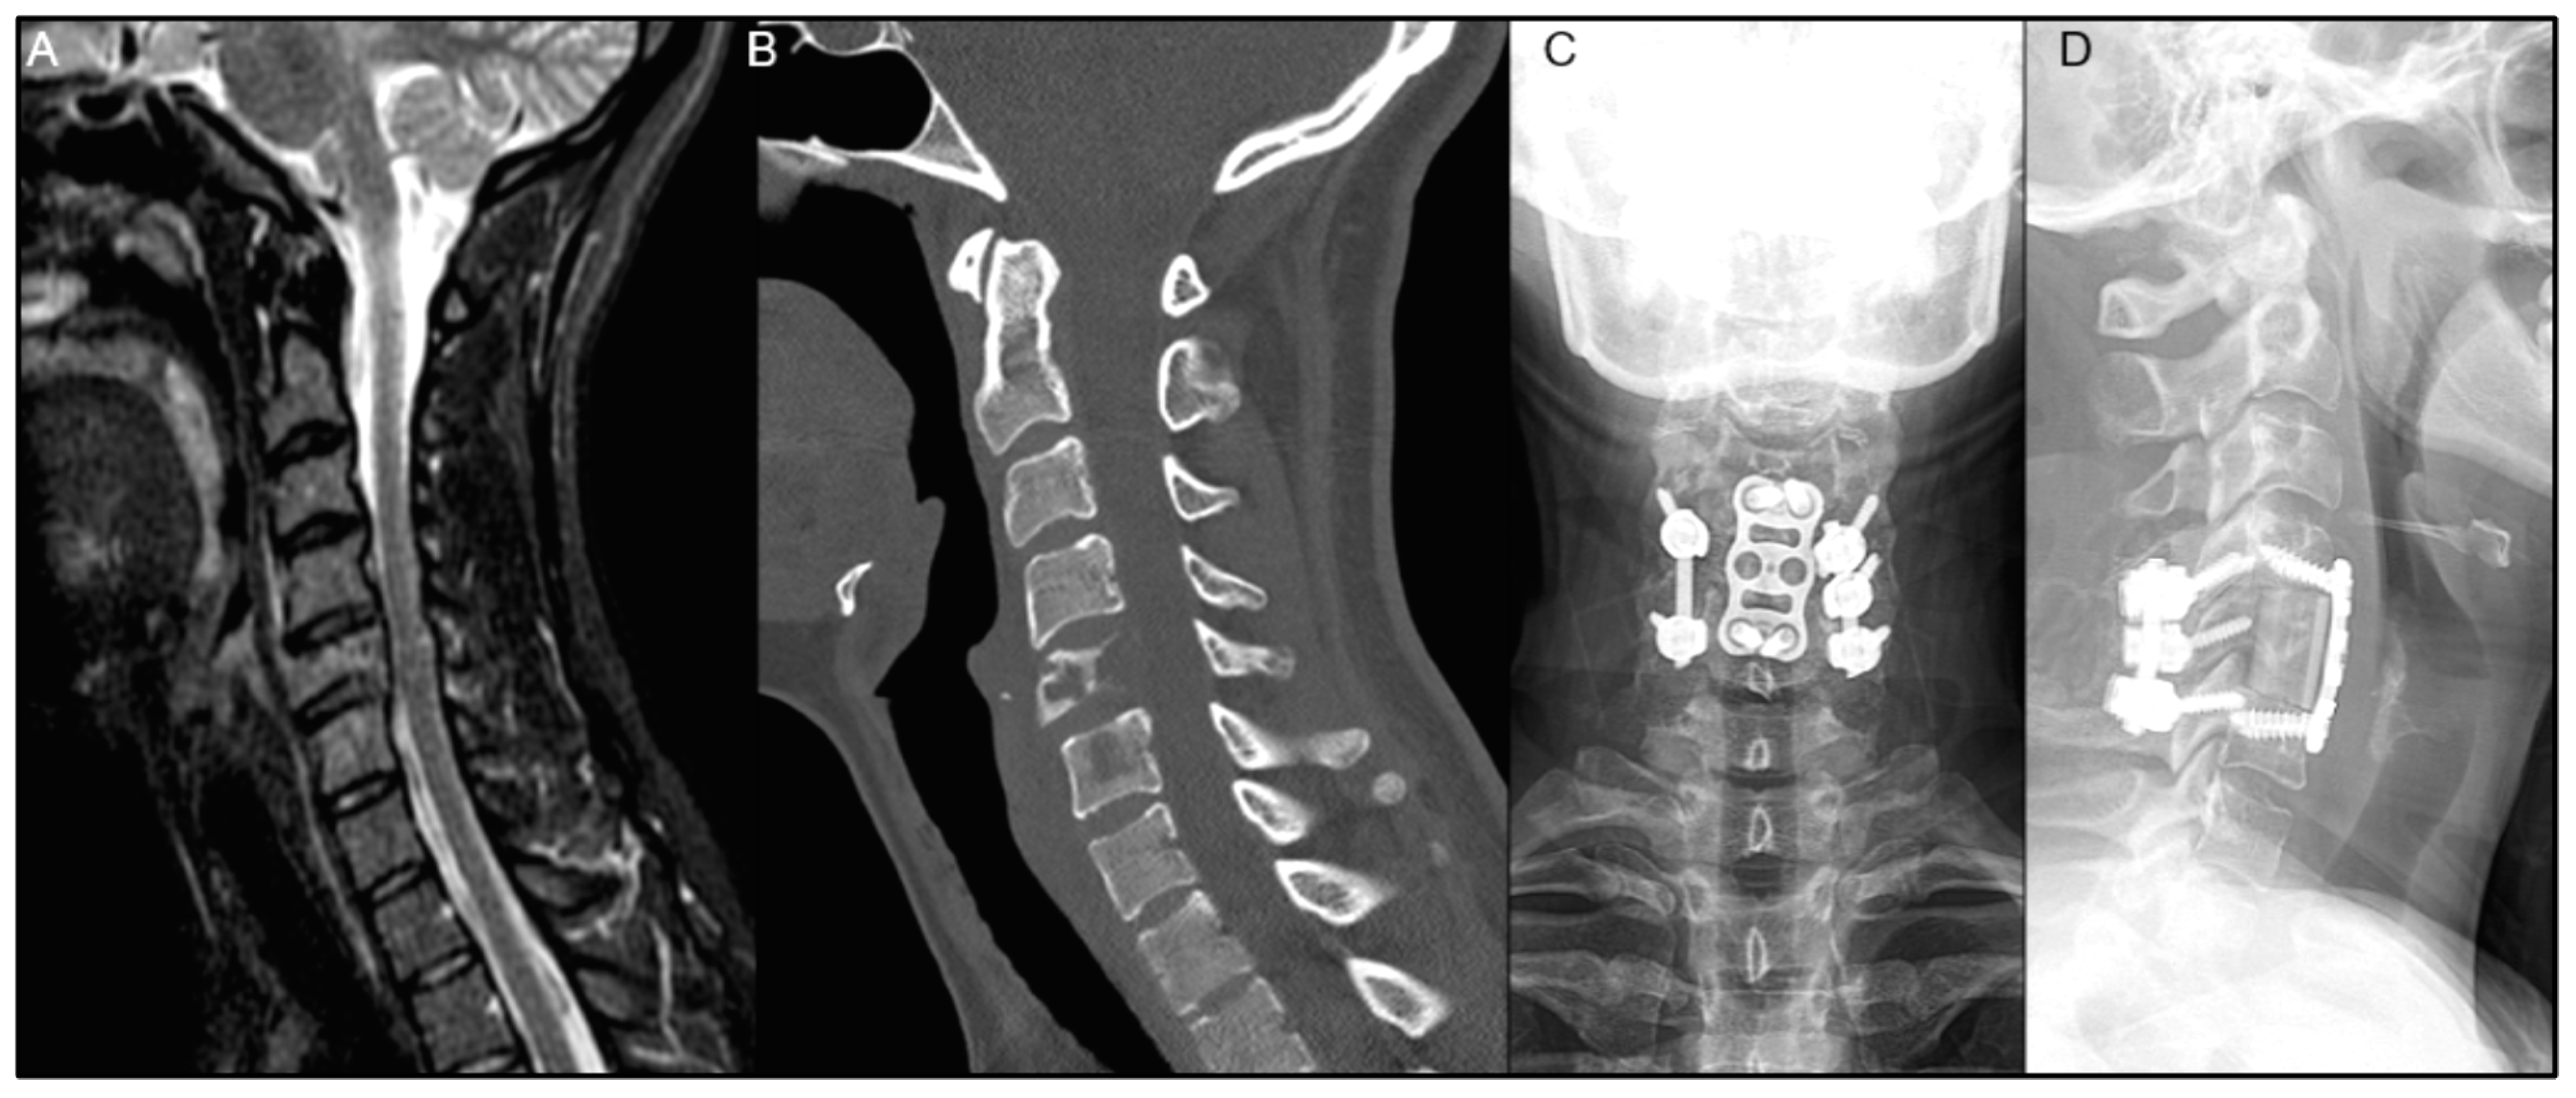

| Patient | Age/Sex | Primary Organ | Instrumented Levels | Radiation | Time to Wound Complication | Reoperation for Wound Complication |

|---|---|---|---|---|---|---|

| 1 | 58M | RCC | T10-L2 | Preop RT only | 48 days | No |

| 2 | 69M | Prostate ADK | T2-T9 | Preop RT only | 39 days | Yes |

| 3 | 44M | Lung ADK | T5-T9 | Postop EBRT | 14 days | Yes |

| 4 | 56F | Lung ADK | O-C5 | Postop EBRT | 22 days | Yes |

| 5 | 72M | Lung ADK | T1-T6 | Postop SBRT | 21 days | Yes |

| 6 | 52M | Lung ADK | C5-T5 | Postop EBRT | 22 days | Yes |

| 7 | 55M | Lung neuroendocrine | T5-T10 | No RT | 43 days | Yes |

| 8 | 67F | Unknown carcinoma | T11-S1 | No RT | 155 days | No |

| 9 | 74F | Lung neuroendocrine | T11-L3 | No RT | 22 days | Yes |

| 10 | 68F | Leiomyosarcoma | L3-S1 | No RT | 23 days | Yes |